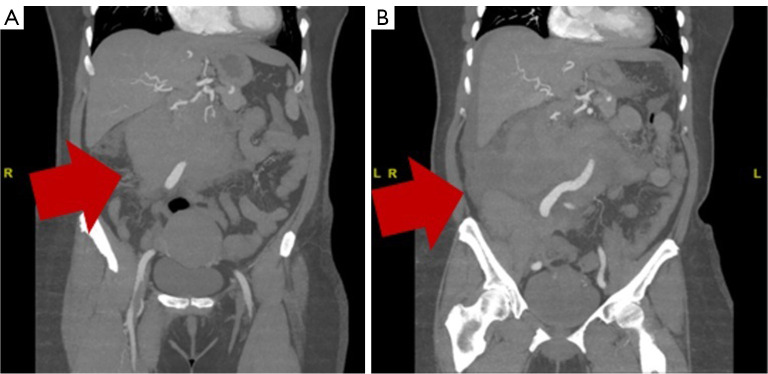

Unveiling the unexpected: spontaneous ruptured pancreaticoduodenal artery pseudoaneurysm with retroperitoneal hematoma requiring pancreaticoduodenectomy.